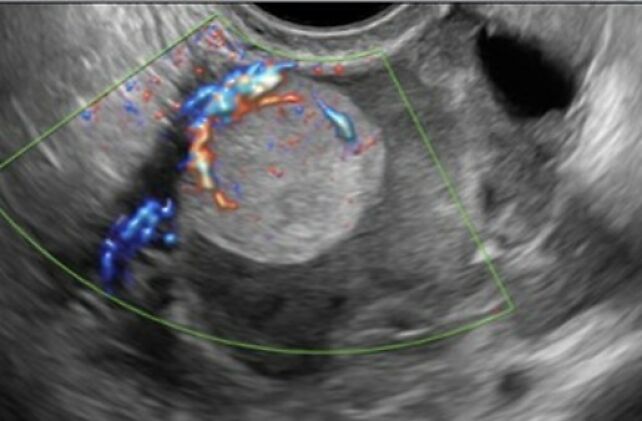

On ultrasound, these tumors appear multilocular-solid (55%), multilocular or solid, with very large dimensions (median diameter of 197 mm) and contain low-level cystic fluid (Figure 6).15

6

Color Doppler ultrasound image of a unilocular-solid mass (46 x 41 x 38 mm) of the right ovary, showing ground-glass echogenicity and a hyperechogenic papillary structure with dimensions of 14 x 20 x 23 mm containing several blood vessels. Color score was 3. Subsequent pathological diagnosis was ovarian mucinous adenocarcinoma with expansive invasion and two foci of infiltrative invasion (maximum diameter of foci of infiltrative invasion <5 mm). FIGO stage IA.